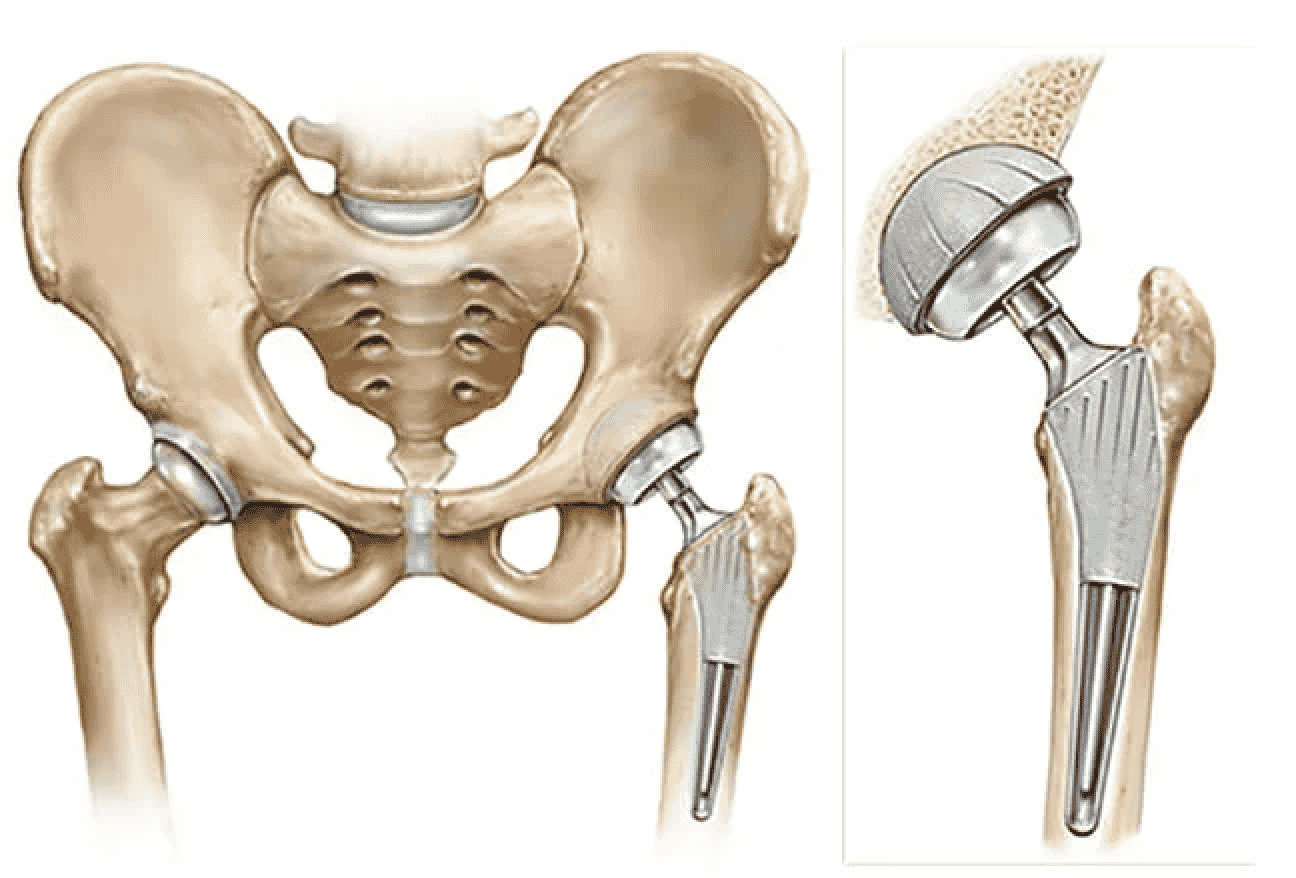

La cirugía de reemplazo de cadera es una opción común y eficaz para quienes sufren de dolor intenso de cadera debido a artritis o lesiones. Este procedimiento puede mejorar drásticamente su calidad de vida, permitiéndole disfrutar de las actividades que disfruta. Ya sea que necesite un reemplazo de cadera parcial o total, Izmir ofrece instalaciones de primera clase y cirujanos expertos para ayudarle en su recuperación.

- Extracción de hueso y cartílago dañados de la articulación de la cadera.

- Inserción del nuevo implante de cadera, ya sea parcial o total.